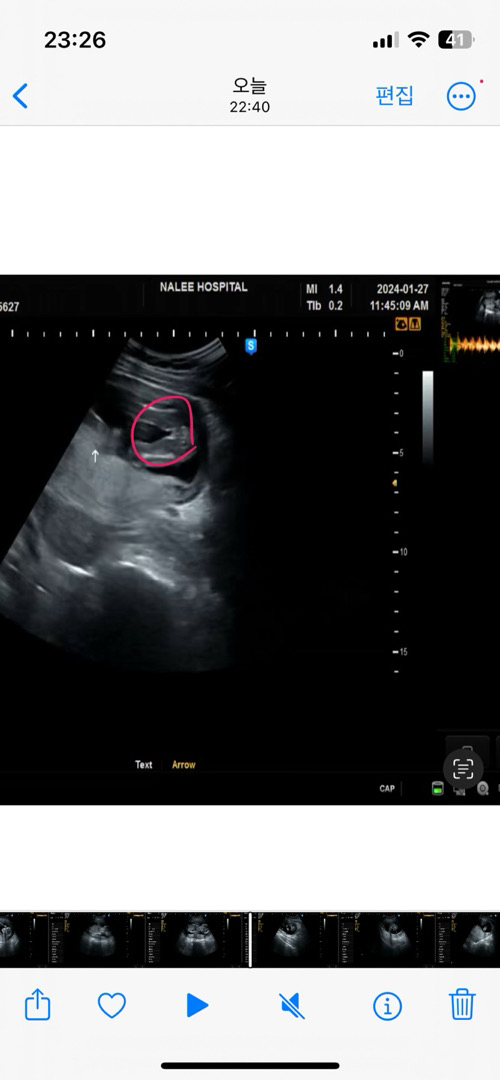

16주 초음파입니다!!!

제가보기에 딸 같은데!! 다른 베동님이 보셨을때도 딸이겠쥬?